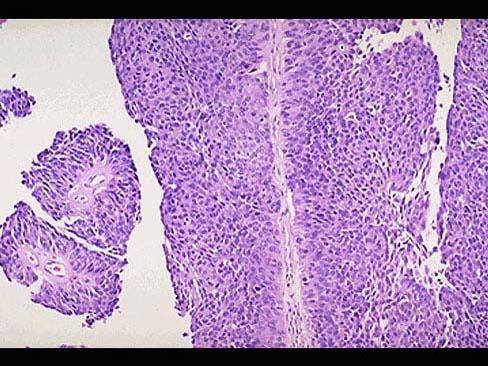

问题 男,65岁。间歇性无痛性肉眼血尿1年。膀胱镜检:膀胱内距输尿管口0.5cm,可见2.5cm×1cm×1cm乳头状肿块,无蒂。静脉肾盂造影可见左肾轻度积水,输尿管全段轻度扩张。行膀胱部分切除后镜检如图所示,下列说法正确的是 ( )

选项 A.该疾病好发部位为膀胱尖部 B.该疾病为膀胱透明细胞癌 C.该疾病手术后不易复发 D.常见的症状为无痛性血尿 E.发生在膀胱的肿瘤大部分为良性

答案 D